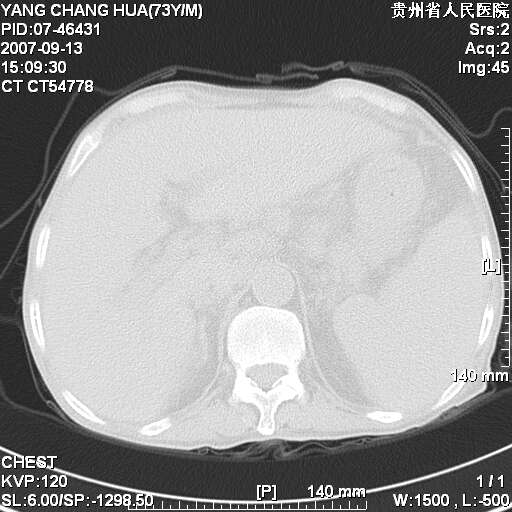

图像没有传全。肺部为感染性病灶;肺囊肿;双侧胸腔积液;肝脾肿大;腹水。

双肺部为感染性病灶.双侧胸腔积液;肝脾肿大;腹水.

双肺部为感染性病灶.双侧胸腔积液;肝脾肿大;脾脏密度不均,不除外脾侵润?腹水.

肝脾肿大。

少量腹水。

双肺散在斑片状及多发小结节状阴影,边缘模糊,双上肺野明显,双侧胸膜腔少量积液,纵隔及肺门区未见明显肿大淋巴结,肝脾肿大,脾内见多发低密度区,结合临床考虑恶性淋巴瘤(肺内表现为肺炎肺泡型),单看影像表现,肺结核不能排除。建议结合实验室检查或表浅淋巴结活检。